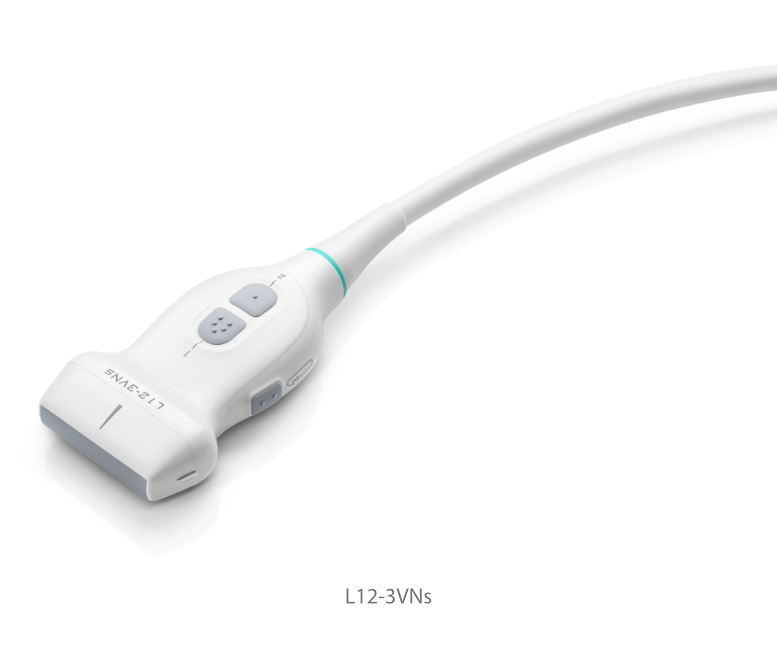

Transducers